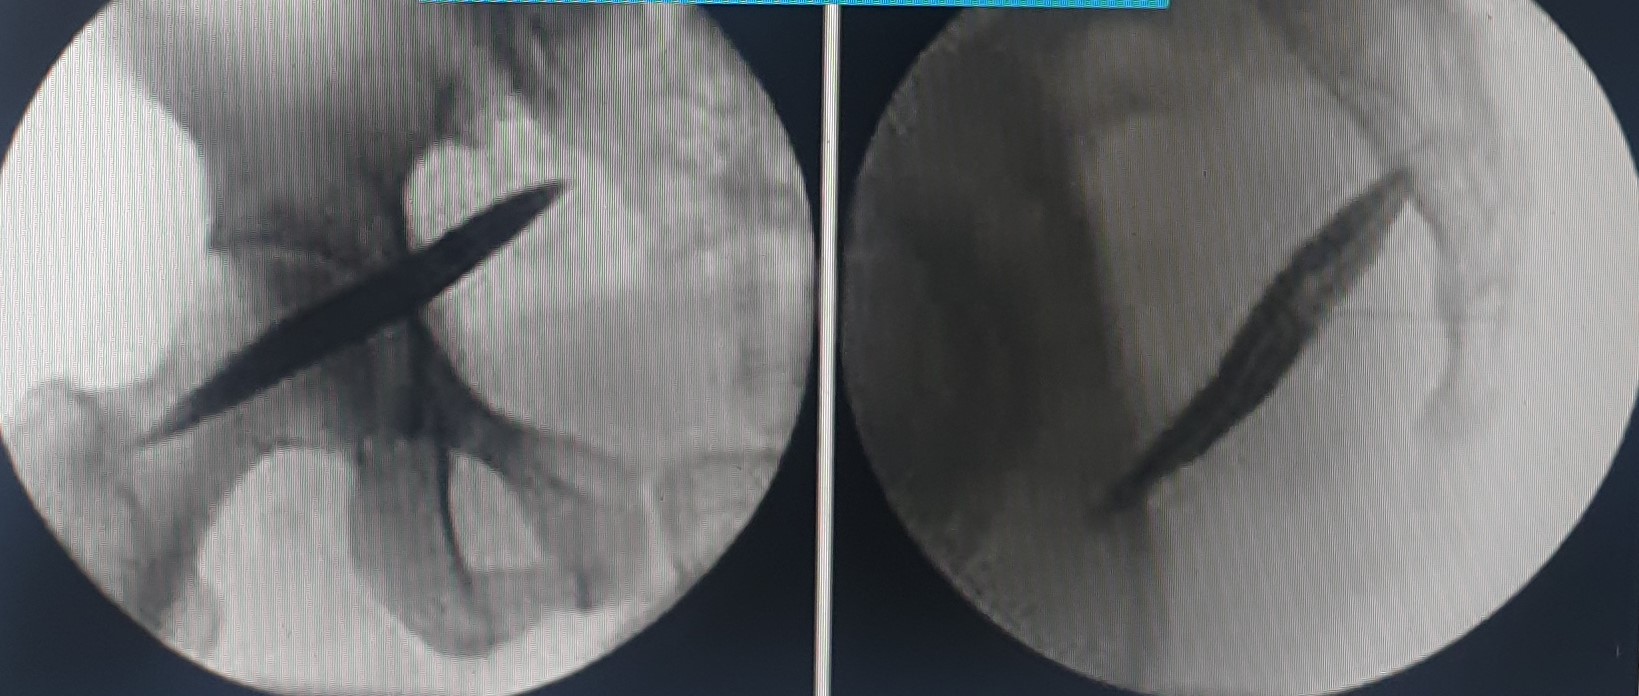

- Κατάλυση των ζυγοαποφυσιακών αρθρώσεων της κατώτερης ΟΜΣΣ και της ιερολαγονίου άρθρωσης με χρήση ραδιοσυχνοτήτων ή κρυοαναλγησίας